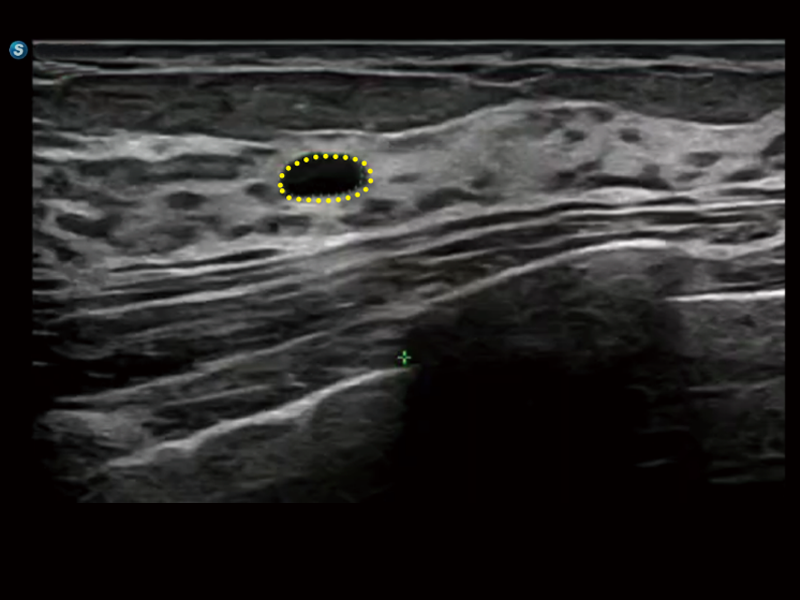

S80 提供多樣化超聲成像技術(shù),可滿足不同科室的需求,在助力掃查診斷和介入治療中發(fā)揮著重要作用。